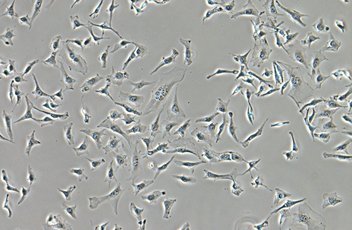

?相差

無論放大倍率范圍如何,均可獲取中性背景色的高對比度圖像。此觀察方法適合觀察沒有染色的結構。 相差附件及物鏡

相差附件及物鏡